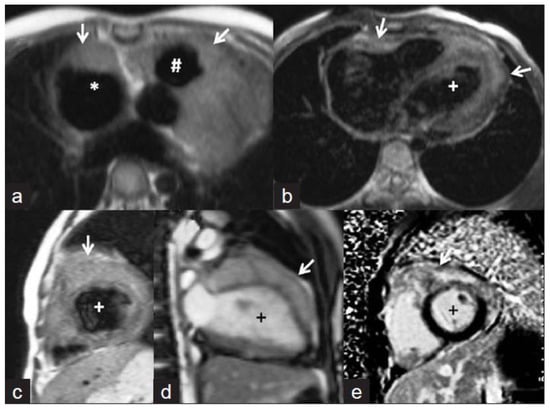

Cardiovascular magnetic resonance imaging is a relatively recent method that shows mild to moderate T2 shortening (Figure 5, This image was adapted from Dixit et al. [53] and 6, This image was adapted from Gulati et al. [47]) comparable to that seen in cerebral tuberculomas with tuberculous involvement [53]. A central isointense core belonging to central caseation, a hypointense rim relating to the fibrous capsule, and a thin hyperintense line about an inflammatory cellular infiltration may all be seen on T2W images [53]. Ring enhancement with conglomeration may be seen on post-gadolinium MRI (Figure 6, This image was adapted from Gulati et al. [47]). Conglomeration develops when a granulomatous lesion is present, which is uncommon in neoplasms [53].

Figure 5.

T2W dark-blood coronal MRI image shows diffuse myopericardial thickening. The thickening is hypointense on T2W images and is causing attenuation of the proximal SVC (arrow). The image was adapted from [53].

Figure 6.

Cardiac magnetic resonance images. (a,b) Axial T1-weighted images showing isointense masses (arrows) along the anterior right atrium (*), right ventricular outflow tract (#), and along both ventricles (+ indicates left ventricle). (c) Short axis T2-weighted image showing that the lesions are mildly hyperintense. (d) Steady-state free precession image revealing the infiltrative nature of the lesion along the left ventricle. The delayed enhanced short-axis image (e) shows heterogeneous enhancement of the mass. The image was adapted from [47].